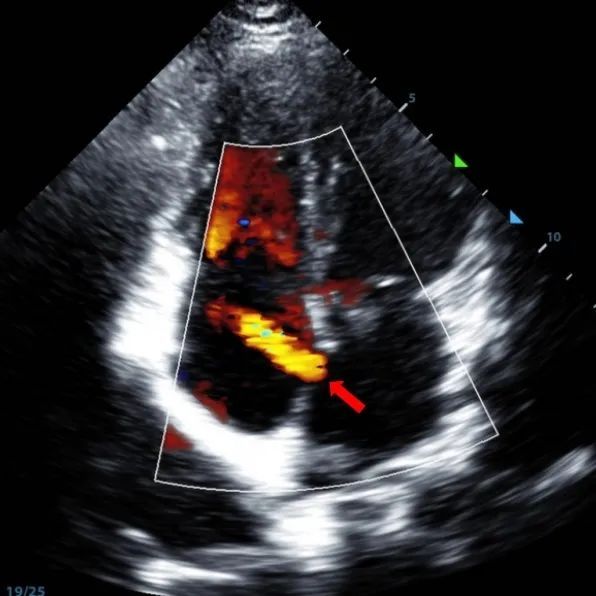

Se trató a un varón de 9 años de edad con ASD secundario (7,5-7,9mm) usando un oclusor de 12mm BDASD-I MemoSorb y un sistema de administración de 12F. No se observaron complicaciones ni comorbilidades antes del procedimiento.

Serial echocardiographic follow-ups showed stable device position and favorable cardiac remodeling. Gradual degradation confirmed the occluder's long-term safety and efficacy.